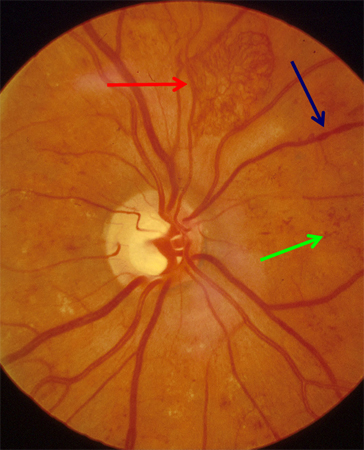

Proliferative diabetic retinopathy: new vessels elsewhere (red arrow), venous beading (blue arrow), intraretinal microvascular abnormality (green arrow)

Courtesy of Moorfields Photographic Archive; used with permission